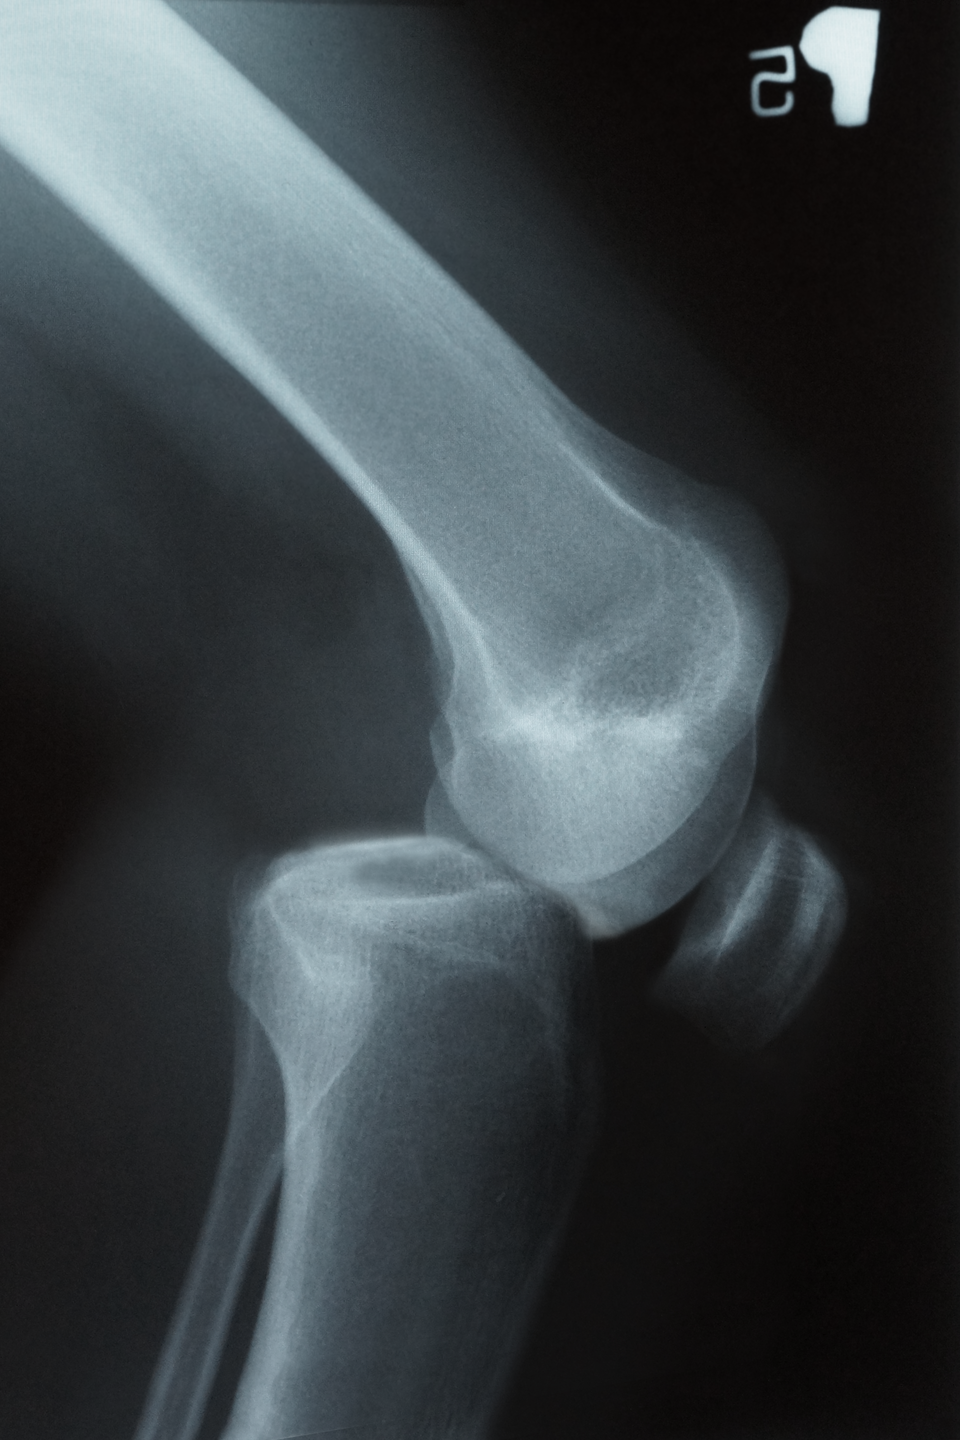

Diagnostyka chorób układu kostnego

Osteoporozę można leczyć dużo skuteczniej przed wystąpieniem objawów chorobowych. Badanie densytometryczne kości umożliwia wykrycie choroby we wczesnym stadium. Jest to nieinwazyjne badanie pozwalające na obrazowanie gęstości kości. Może być ono wykonane przy użyciu metody ultrasonograficznejultrasonograficznej (USG), tomografii komputerowejtomografii komputerowej lub rentgenowskiej.

Najczęściej stosowaną jest ostatnia z metod, w której kości prześwietla się za pomocą promieni rentgenowskichpromieni rentgenowskich o małym natężeniu. Bogate w wapń kości mają dużą gęstość i obficie pochłaniają promieniowanie. Po wykonaniu badania jego wynik porównuje się z wartościami normalnymi gęstości kości dla danego wieku pacjenta. Dla wygody gęstość kości przestawia się na wykresie w postaci wskaźnika T, którego wartość wynosi zero (wartość normalna) dla młodego 30. letniego mężczyzny. Wartości dodatnie wskaźnika T uzyskanego w badaniu sugerują zwiększoną gęstość kości (np. przy nadmiernym zwapnieniu kości). Jego ujemne wartości z kolei wskazują na zmniejszoną gęstość kości. Jeśli wartość wskaźnika T znajduje się w zakresie od −1 do −2,5, stwierdza się stan obniżonej gęstości kości (osteopenia), który może rozwinąć się w osteoporozę – wskaźnik T mniejszy niż −2,5.

Złamania kości polegają na przerwaniu ciągłości kości. Wymagają diagnostyki obrazowej, unieruchomienia, a czasem operacji.